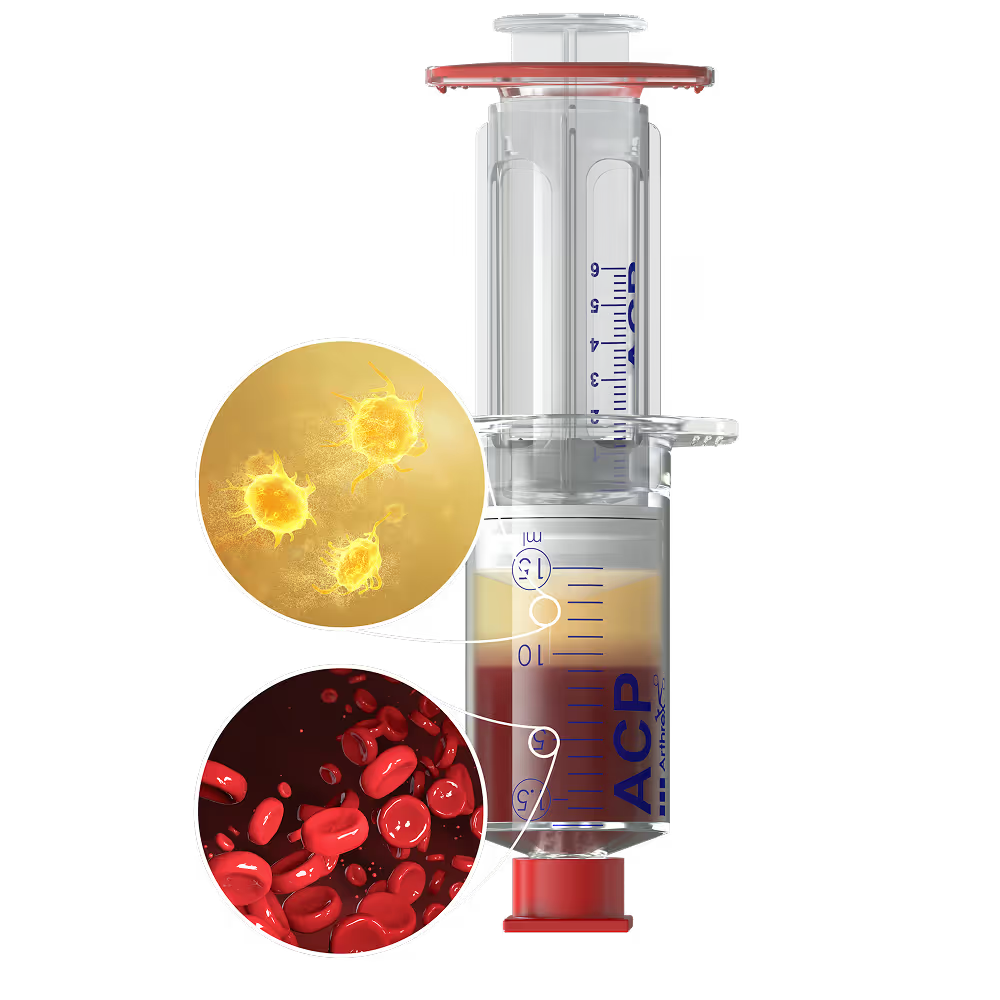

Each of our biologic principles is supported by targeted solutions designed for intraoperative use. Arthrex combines the following biologic elements with proven mechanical stability:

Matrix

Provides structural support and guides cellular integration

Regenerative Cells

Contribute to tissue formation and repair

Growth Factors

Reduce inflammation and activate healing pathways